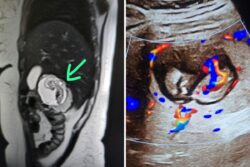

UP Woman’s Foetus Growing In Liver, Not Uterus: Only 8 such cases reported worldwide. Meerut...